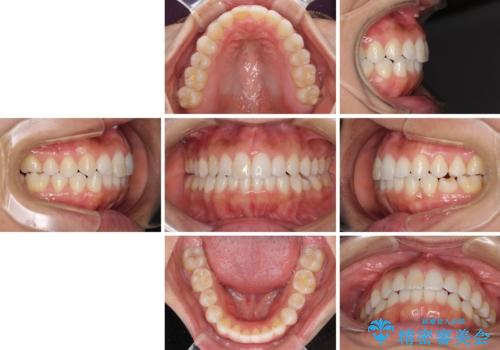

- 上下の前歯のデコボコと奥歯の反対咬合を気にして来院された患者様です。

インビザラインを用い、上下顎ともにIPR(歯と歯の間を削る)により叢生を改善することとしました。

奥歯の反対咬合は、骨格に由来するものであるため、改善できるところまで改善していくこととしました。

治療を長期化させたくないとのご要望があったので、左下の90度捻転した歯は、捻転した状態のゴールとしました。

反対咬合を改善したことで、歯ぎしりしたときの引っかかる感じがなくなり、奥歯への負担を大きく軽減することができました。